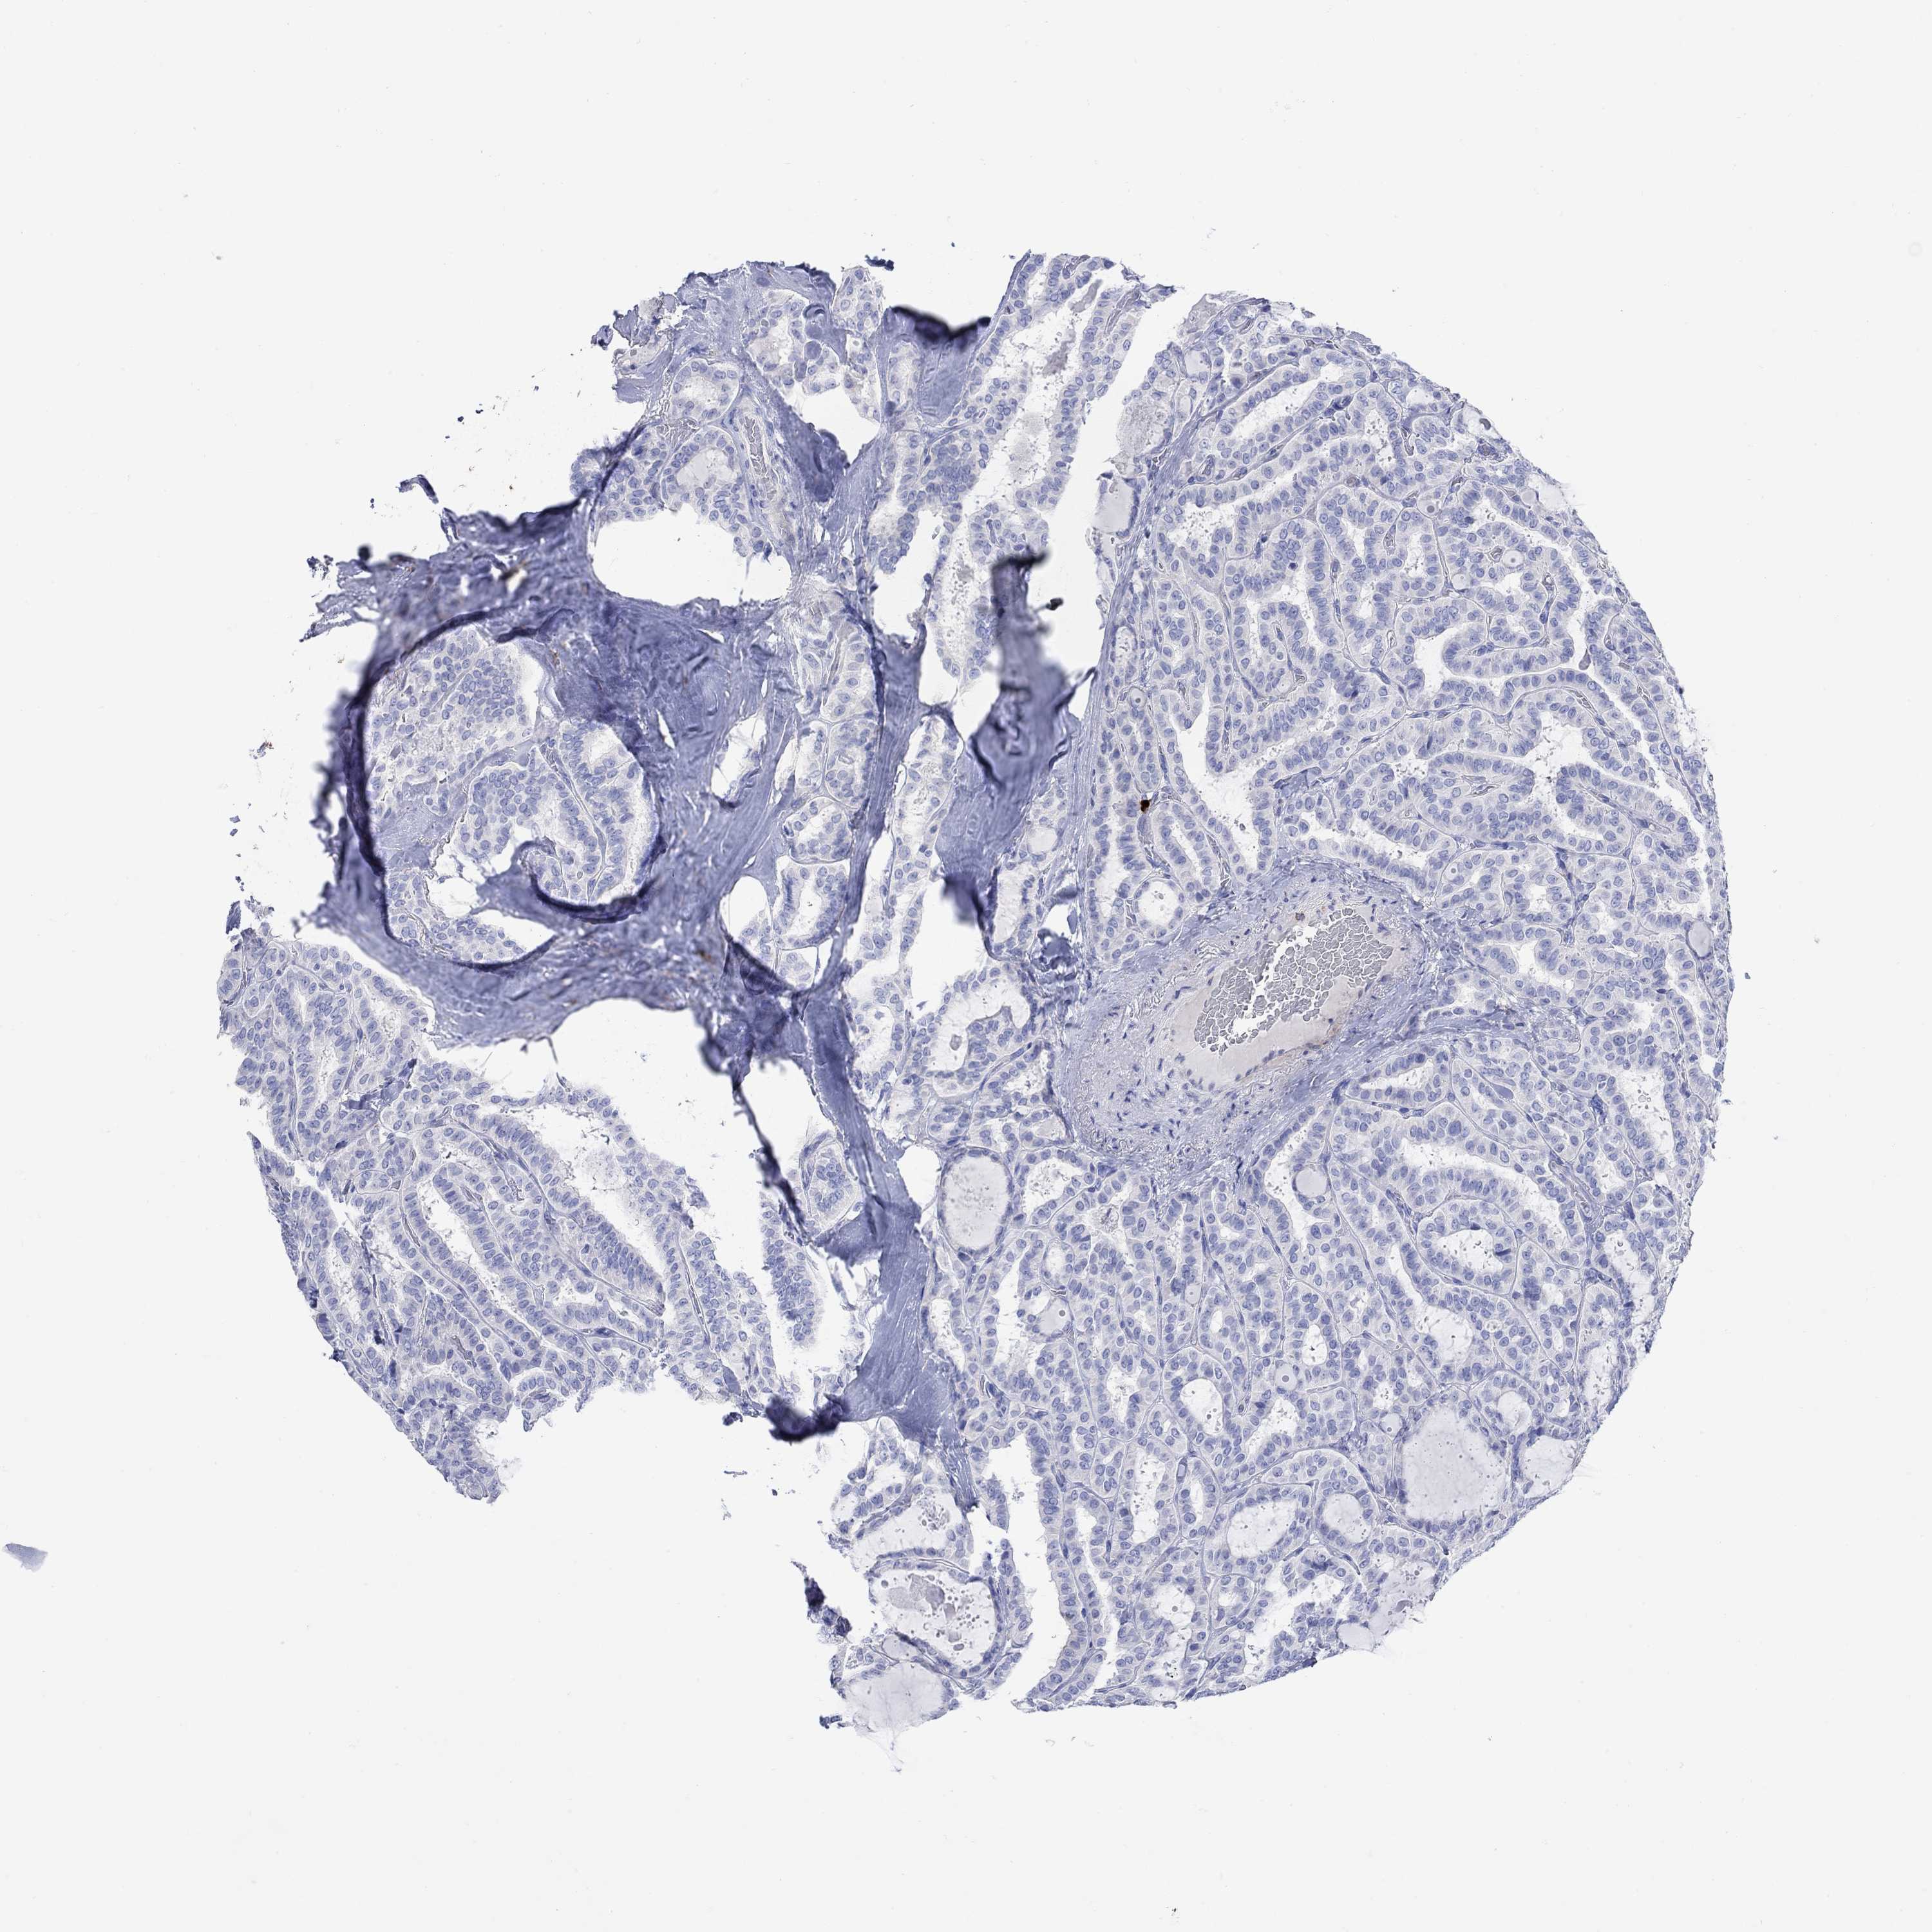

THYROID CANCER - Protein expressioni

A mouse-over function shows sample information and annotation data. Click on an image to view it in a full screen mode. Samples can be filtered based on level of antibody staining by selecting one or several of the following categories: high, medium, low and not detected. The assay and annotation is described here.

Note that samples used for immunohistochemistry by the Human Protein Atlas do not correspond to samples in the TCGA dataset.

Antibody stainingi

Antibody staining in the annotated cell types in the current human tissue is reported as not detected, low, medium, or high, based on conventional immunohistochemistry profiling in selected tissues. This score is based on the combination of the staining intensity and fraction of stained cells.

Each image is clickable and will lead to virtual microscopy that enables deeper exploration of all samples and also displays staining intensity scores, fraction scores and subcellular localization as well as patient and tissue information for each sample.

Antibody HPA074751

Staining

High

Medium

Low

Not detected

Intensity

Strong

Moderate

Weak

Negative

Quantity

>75%

75%-25%

<25%

None

Location

Nuclear

Cytoplasmic/membranous

Cytoplasmic/membranous,nuclear

Papillary adenocarcinoma, NOS

Follicular adenoma carcinoma, NOS